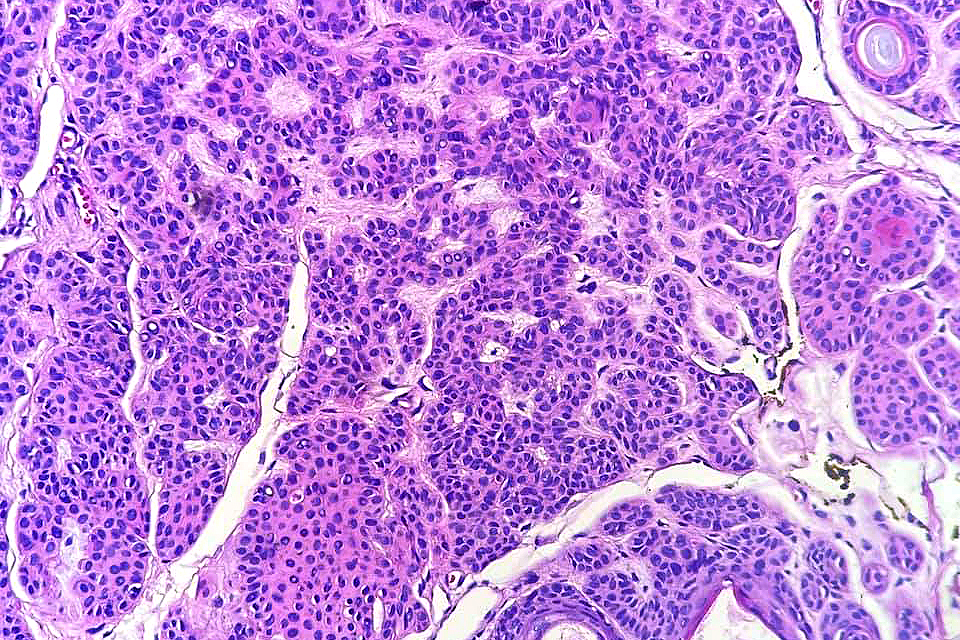

•Vertically orientated, folliculocentric, thin, anastomosing strands composed of basaloid cells embedded in a loose fibrous stroma

•No pleomorphism

•No mitoses

•+/- peripheral palisading